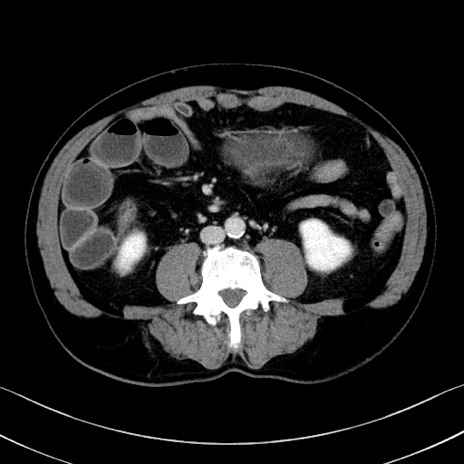

症例35(横断像)

【症例】70歳代 男性

【主訴】腹部膨満、嘔吐

【現病歴】昨日より腹部膨満感出現。本日増悪し、仙痛出現。嘔吐あり、受診。

【既往歴】糖尿病、胆摘後

【身体所見】BP 149/80mmHg、HR 74/min、BT 35.9℃、腹部:膨満、軟、圧痛なし。腸雑音減弱あり。上腹部正中切開瘢痕あり。

【データ】WBC 13500、CRP 1.72